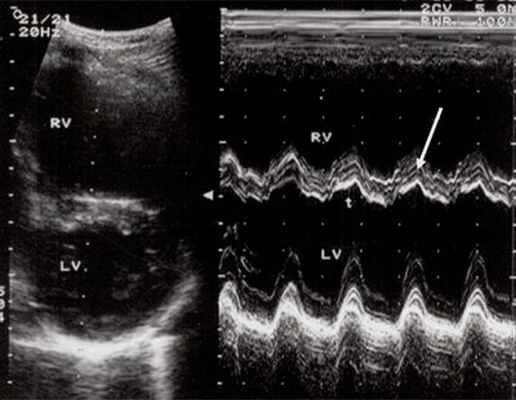

Характерными особенностями выраженной объемной перегрузки правого желудочка являются дилатация желудочка, при которой толщина миокарда не превышает верхней границы нормы, увеличение правого предсердия, парадоксальный характер движения межжелудочковой перегородки и увеличение амплитуды движения трикуспидального клапана (рис. 2, 3).

Рис. 3. Объемная перегрузка правого желудочка при дефекте межпредсердной перегородки. В- и М-сканирование. Стрелкой показан парадоксальный характер движения межжелудочковой перегородки.